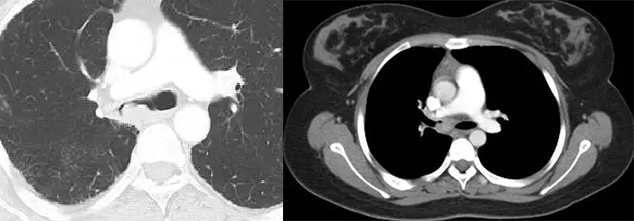

单发肺转移

无恶性肿瘤病史的患者单发肺转移的发生率很低(0.4 ~ 9.0%),有恶性肿瘤史的患者发生单发肺结节时 25 ~ 46% 为转移,且原发肿瘤多为腺癌或软组织肉瘤等。Cahan 总结 800 例肺孤立性肿物提出以下原则:原发肿瘤为鳞癌时肺内肿物多为原发,为腺癌时肺内原发和转移的概率各半,原发为软组织或骨肉瘤、黑色素瘤时肺内多为转移。CT 上单发转移瘤多数边缘光整,符合转移瘤特点,少数边缘可出现分叶、毛刺等,与原发肿瘤难以鉴别。

直肠癌术后 2 年,发现右肺结节 1 周。双肺仅见 1 枚结节,穿刺活检证实为直肠癌转移。